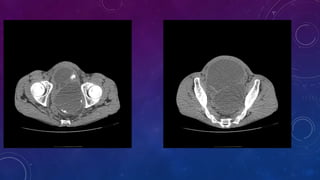

Bladder exstrophy or ectopia vesicae is characterized by deficient lower anterior abdominal wall

along with anterior walls of urinary bladder. The severity of these defects is widely variable. There

may be rudimentary posterior wall of urinary bladder.

The estimated incidence of bladder exstrophy is 1:10,000-50,000 live births. There is a recognized

male predilection with a male to female ratio of 3:1 . Most cases are sporadic.

Associated bony findings include widely separated pubic bones with absent symphysis pubis

leading to characteristic " waddling gait". This appearance on AP plain radiograph of the pelvis has

been likened to a manta ray swimming towards you (manta ray sign).

Bladder exstrophy is caused by a developmental defect of the cloacal membrane.

Associated defects in males include cryptorchidism, inguinal hernia and epispadia.

Associated defects in females include vaginal duplication and clitoral cleft. This is associated

prenatally with elevated maternal alpha feto protein levels.

Common complications include urinary incontinence, infertility, urinary infections and

increased risk of bladder malignancy in the extruded bladder. Treatment is with surgical

intervention (primary closure/excision with urinary diversion) and prognosis is generally

good.